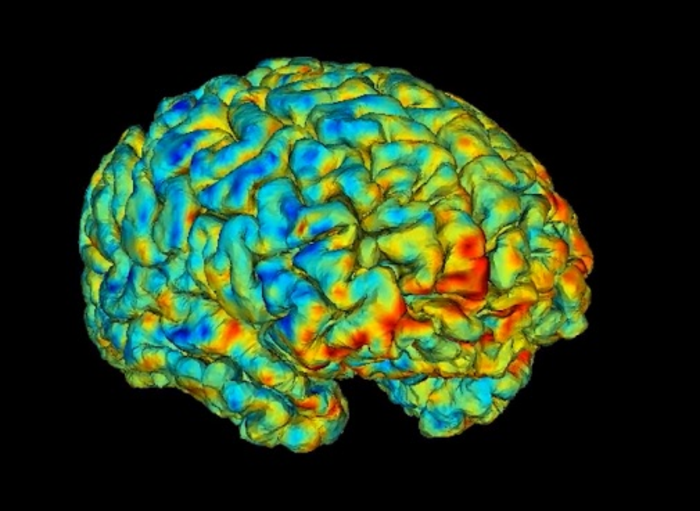

• Cambridge team uses powerful new MRI scans to enable life-changing surgery in first for adults with epilepsy

Cambridge team uses powerful new MRI scans to enable life-changing surgery in first for adults with epilepsy